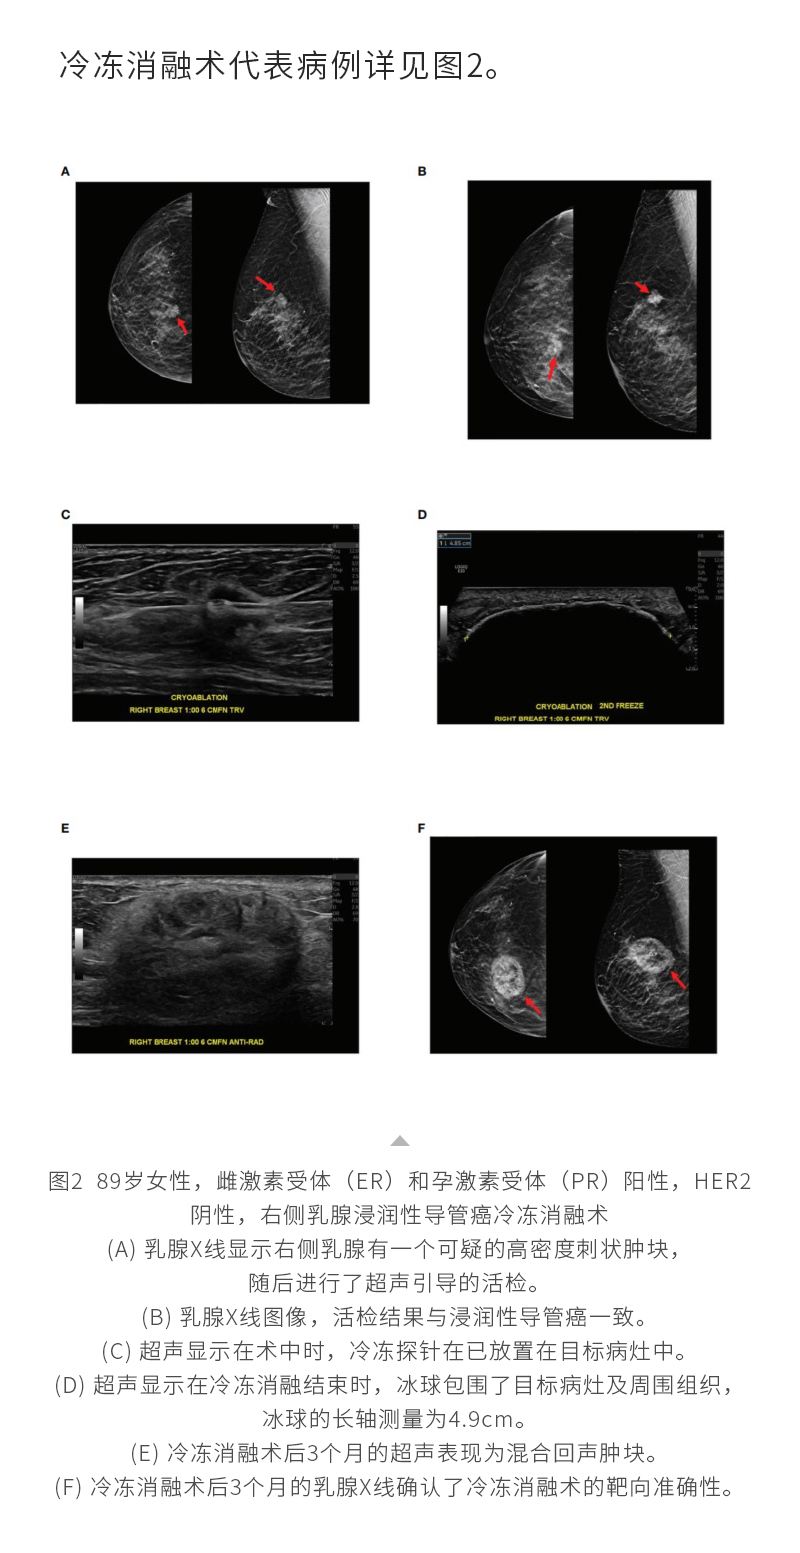

冷凍消融乳腺癌——【海杰亞科研資訊】第287期

發(fā)布時(shí)間:2024-10-28 | 作者:海杰亞 | 瀏覽次數(shù):708